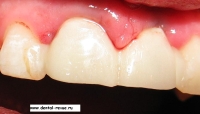

26. Временные коронки сразу после установки при сомкнутых зубах.